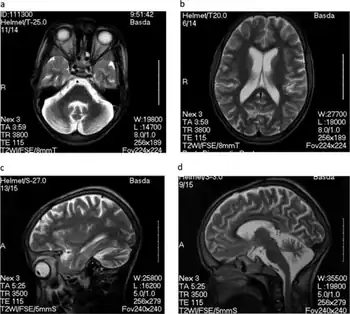

Children affected by nodding disease experience a complete and permanent stunting of growth. The growth of the brain is also stunted, leading to mental handicap. The disease is named for the characteristic, pathological nodding seizure, which often begins when the children begin to eat, or sometimes when they feel cold.[6] These seizures are brief and halt after the children stop eating or when they feel warm again. Seizures in nodding disease span a wide range of severity. Neurotoxicologist Peter Spencer, who has investigated the disease, has stated that upon presentation with food, "one or two [children] will start nodding very rapidly in a continuous, pendulous nod. A nearby child may suddenly go into a tonic–clonic seizure, while others will freeze."[7] Severe seizures can cause the child to collapse, leading to further injury.[8] Sub-clinical seizures have been identified in electroencephalograms, and MRI scans have shown brain atrophy and damage to the hippocampus and glia cells.[5]